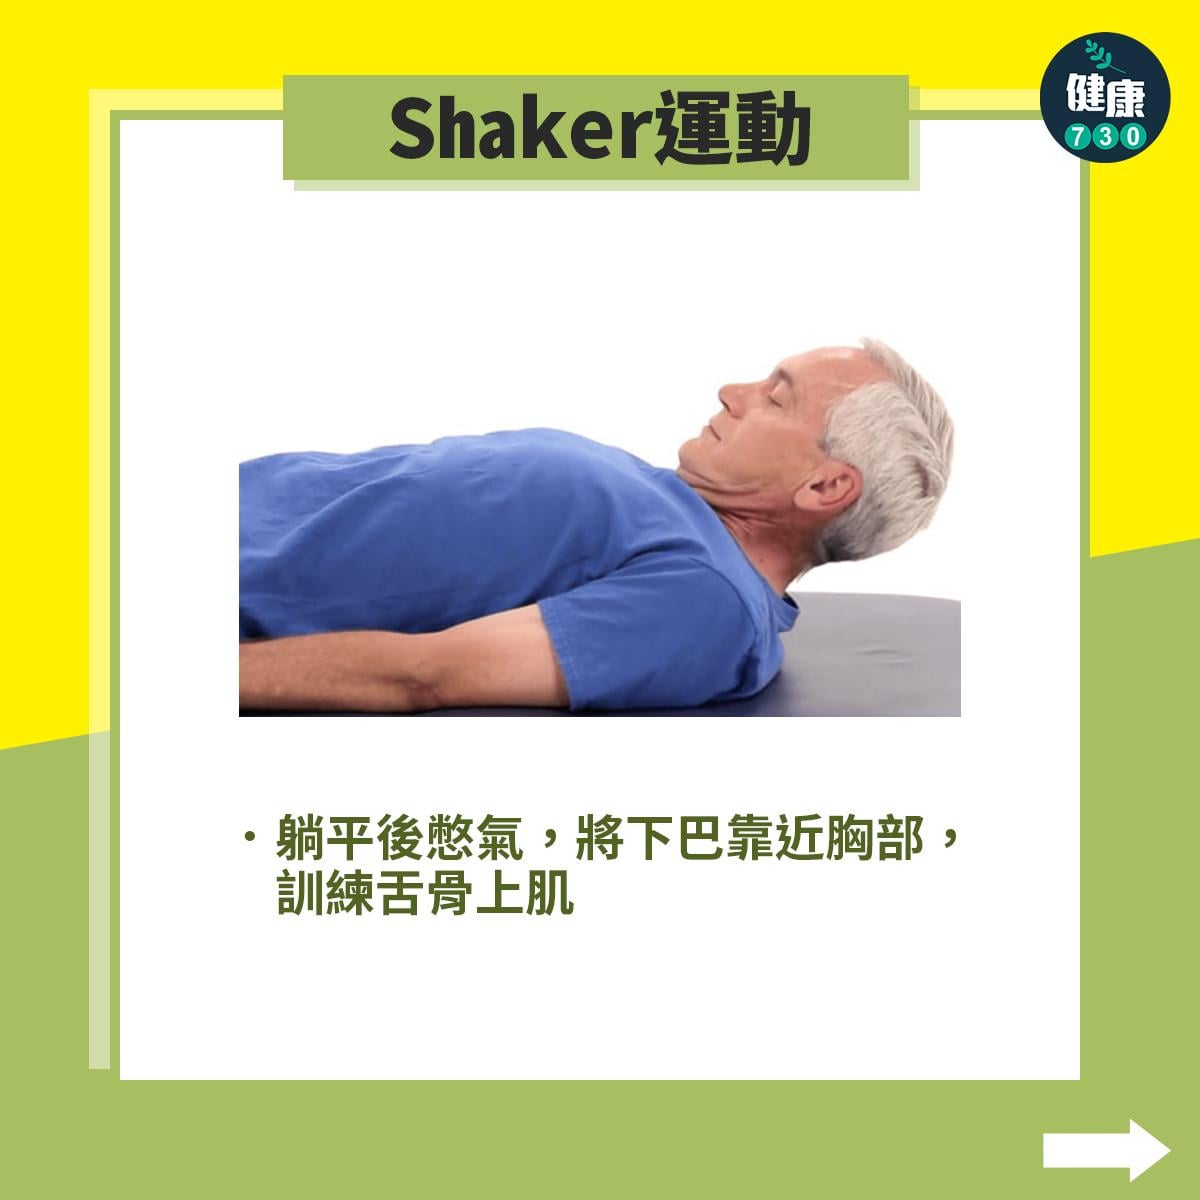

中風復健|5招改善中風後吞嚥困難